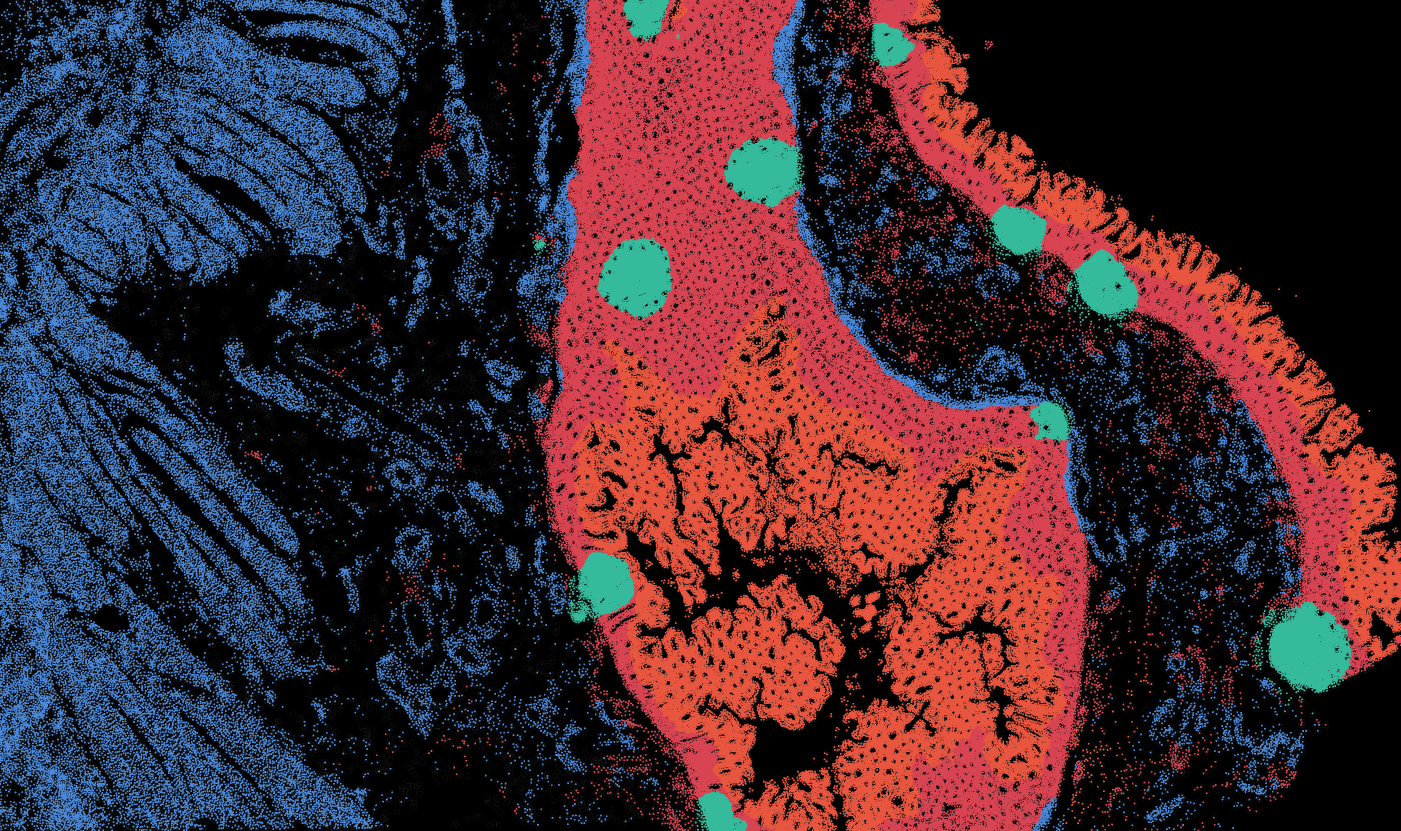

Applicability across different spatial resolutions

The segmentation module is designed to help researchers explore tissue architecture at multiple levels of detail, depending on their scientific question. Users can begin by dividing the tissue into major anatomical structures to gain a broad overview of the spatial landscape. From there, they can zoom into a specific region of interest and further segment it into sub-tissue compartments, enabling more refined analysis of microenvironments and localized biological processes.

Streamline multi-omics data collaboration

OmnibusX brings research teams even closer together. Pathologists can now seamlessly annotate tissue images, providing critical insights that drive deeper biological analysis for every team member.